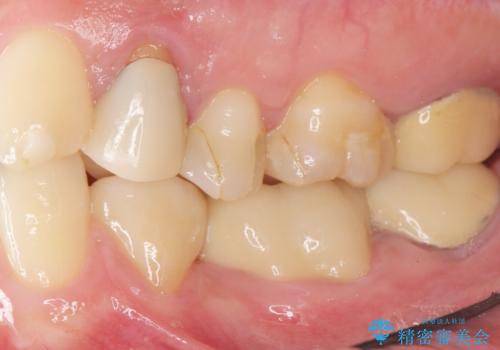

矯正は絶対にしたくないという強いご希望により、舌側転位している歯を抜去し歯肉の治癒を待ったのち、両隣の歯の補綴治療を行いました。

セラミッククラウンにより、抜歯した部分のスペースを閉じ歯並びを整えました。